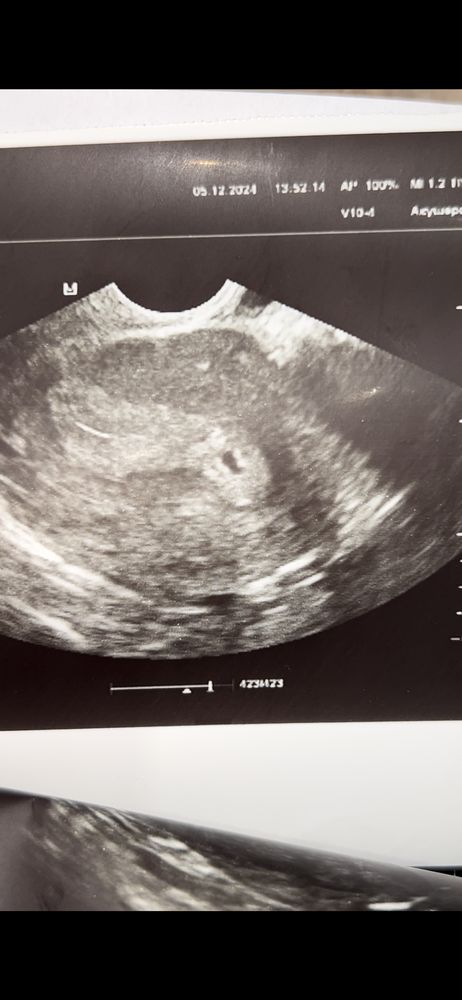

Беременность малого срока

Многоплодная беременность

Добрый вечер) подскажите пожалуйста, вчера сделала УЗИ, беременность малого срока. И разглядываю вот картинку и не пойму что это такое. Плодное яйцо это понятно, а вот что за две точки белые? Это просто неровность же?

подскажите пожалуйста, кто разбирается